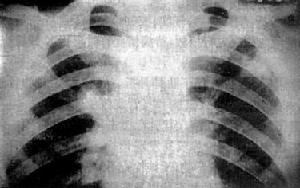

肺諾卡菌病X線圖起病緩急不一。免疫功能低下者常呈急性起病。全身症狀有發熱,疲乏無力,厭食等。呼吸道症狀有咳嗽,黏稠膿痰,量通常不多,胸痛,氣急,咯血等。胸壁有時可見瘺管。不治療或治療延誤則轉成慢性,出現類似肺結核病的慢性感染的相應表現。胸部X線呈現炎症浸潤、實變、單發或多髮結節狀陰影,經常有膿腫和空洞形成,偶見厚壁空洞。病變分布以

臨床症狀初為乾咳,繼之為粘稠膿性痰,後期咳膿臭痰,痰中可帶血,常有發熱、盜汗、胸痛及消瘦等,體溫多為38~C~40~C。可出現胸腔積液或膿胸,少數可穿破胸壁至皮膚形成瘺管,也可波及腹腔、內臟或經血循環播散至全身。x線胸片早期表現為炎性浸潤類似小葉性或大葉性肺炎,也可表現為單發或多髮結節影,可發現厚壁透光區,代表多發性小膿腫形成的空洞。還可伴有肺門淋巴結腫大,但很少有鈣化。病變可累及一葉或多葉。有時呈水皰性或壞疽性改變,表麵皮膚為粉紅色,其後迅速擴展並破潰,其上有粘性黃白色膿液;向周圍擴散後引起全足腫脹,足趾變形。也可向深部組織及骨擴展,形成多數膿腫、相互交通的竇道、瘺管及骨質破壞等。分泌物呈漿液狀、膿性或油狀,常帶白色、黃色或黑色顆粒。病原菌最常播散部位是在大腦引起腦膿腫,其次是在腎臟引起腎膿腫等,也可引起心內膜炎、心肌炎、心包炎,肝、脾、腎上腺、胃腸、淋巴結、肋骨、椎骨、骨盆及關節也可受累,胰腺、甲狀腺、眼、耳、脊椎、垂體及膀胱較少累及。病變以局部膿腫最為常見。臨床感染徵象突出,常有發熱,多部位膿腫,多器官損害,預後不良。臨床診斷本病臨床表現無特異性,如有前述部位感染徵象而排除其他疾病時可考慮本病的可能性。尤其是臨床上同時有“腦瘤”或多發性皮膚膿腫者,更應考慮血行播散性諾卡菌病,及時進行諾卡菌病原學檢查確診。

其他輔助檢查:胸部X 線呈現炎症浸潤、實變、單發或多髮結節狀陰影,經常有膿腫和空洞形成,偶見厚壁空洞。病變分布以兩下葉多見,亦可呈粟粒樣或瀰漫性間質性浸潤,極少鈣化和纖維化,約1/3 患者並發膿胸。